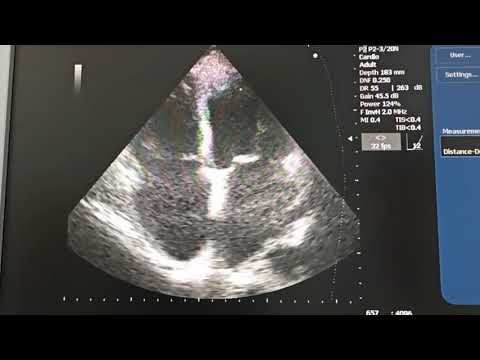

Фракция выброса левого желудочка по Тейхольцу, Симпсону и Думеснилу доплеровский метод

ЭхоКГ FOCUS